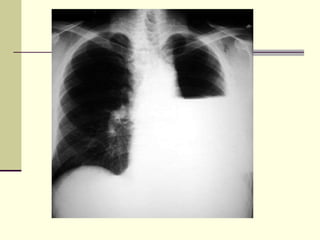

 CXR

CXR